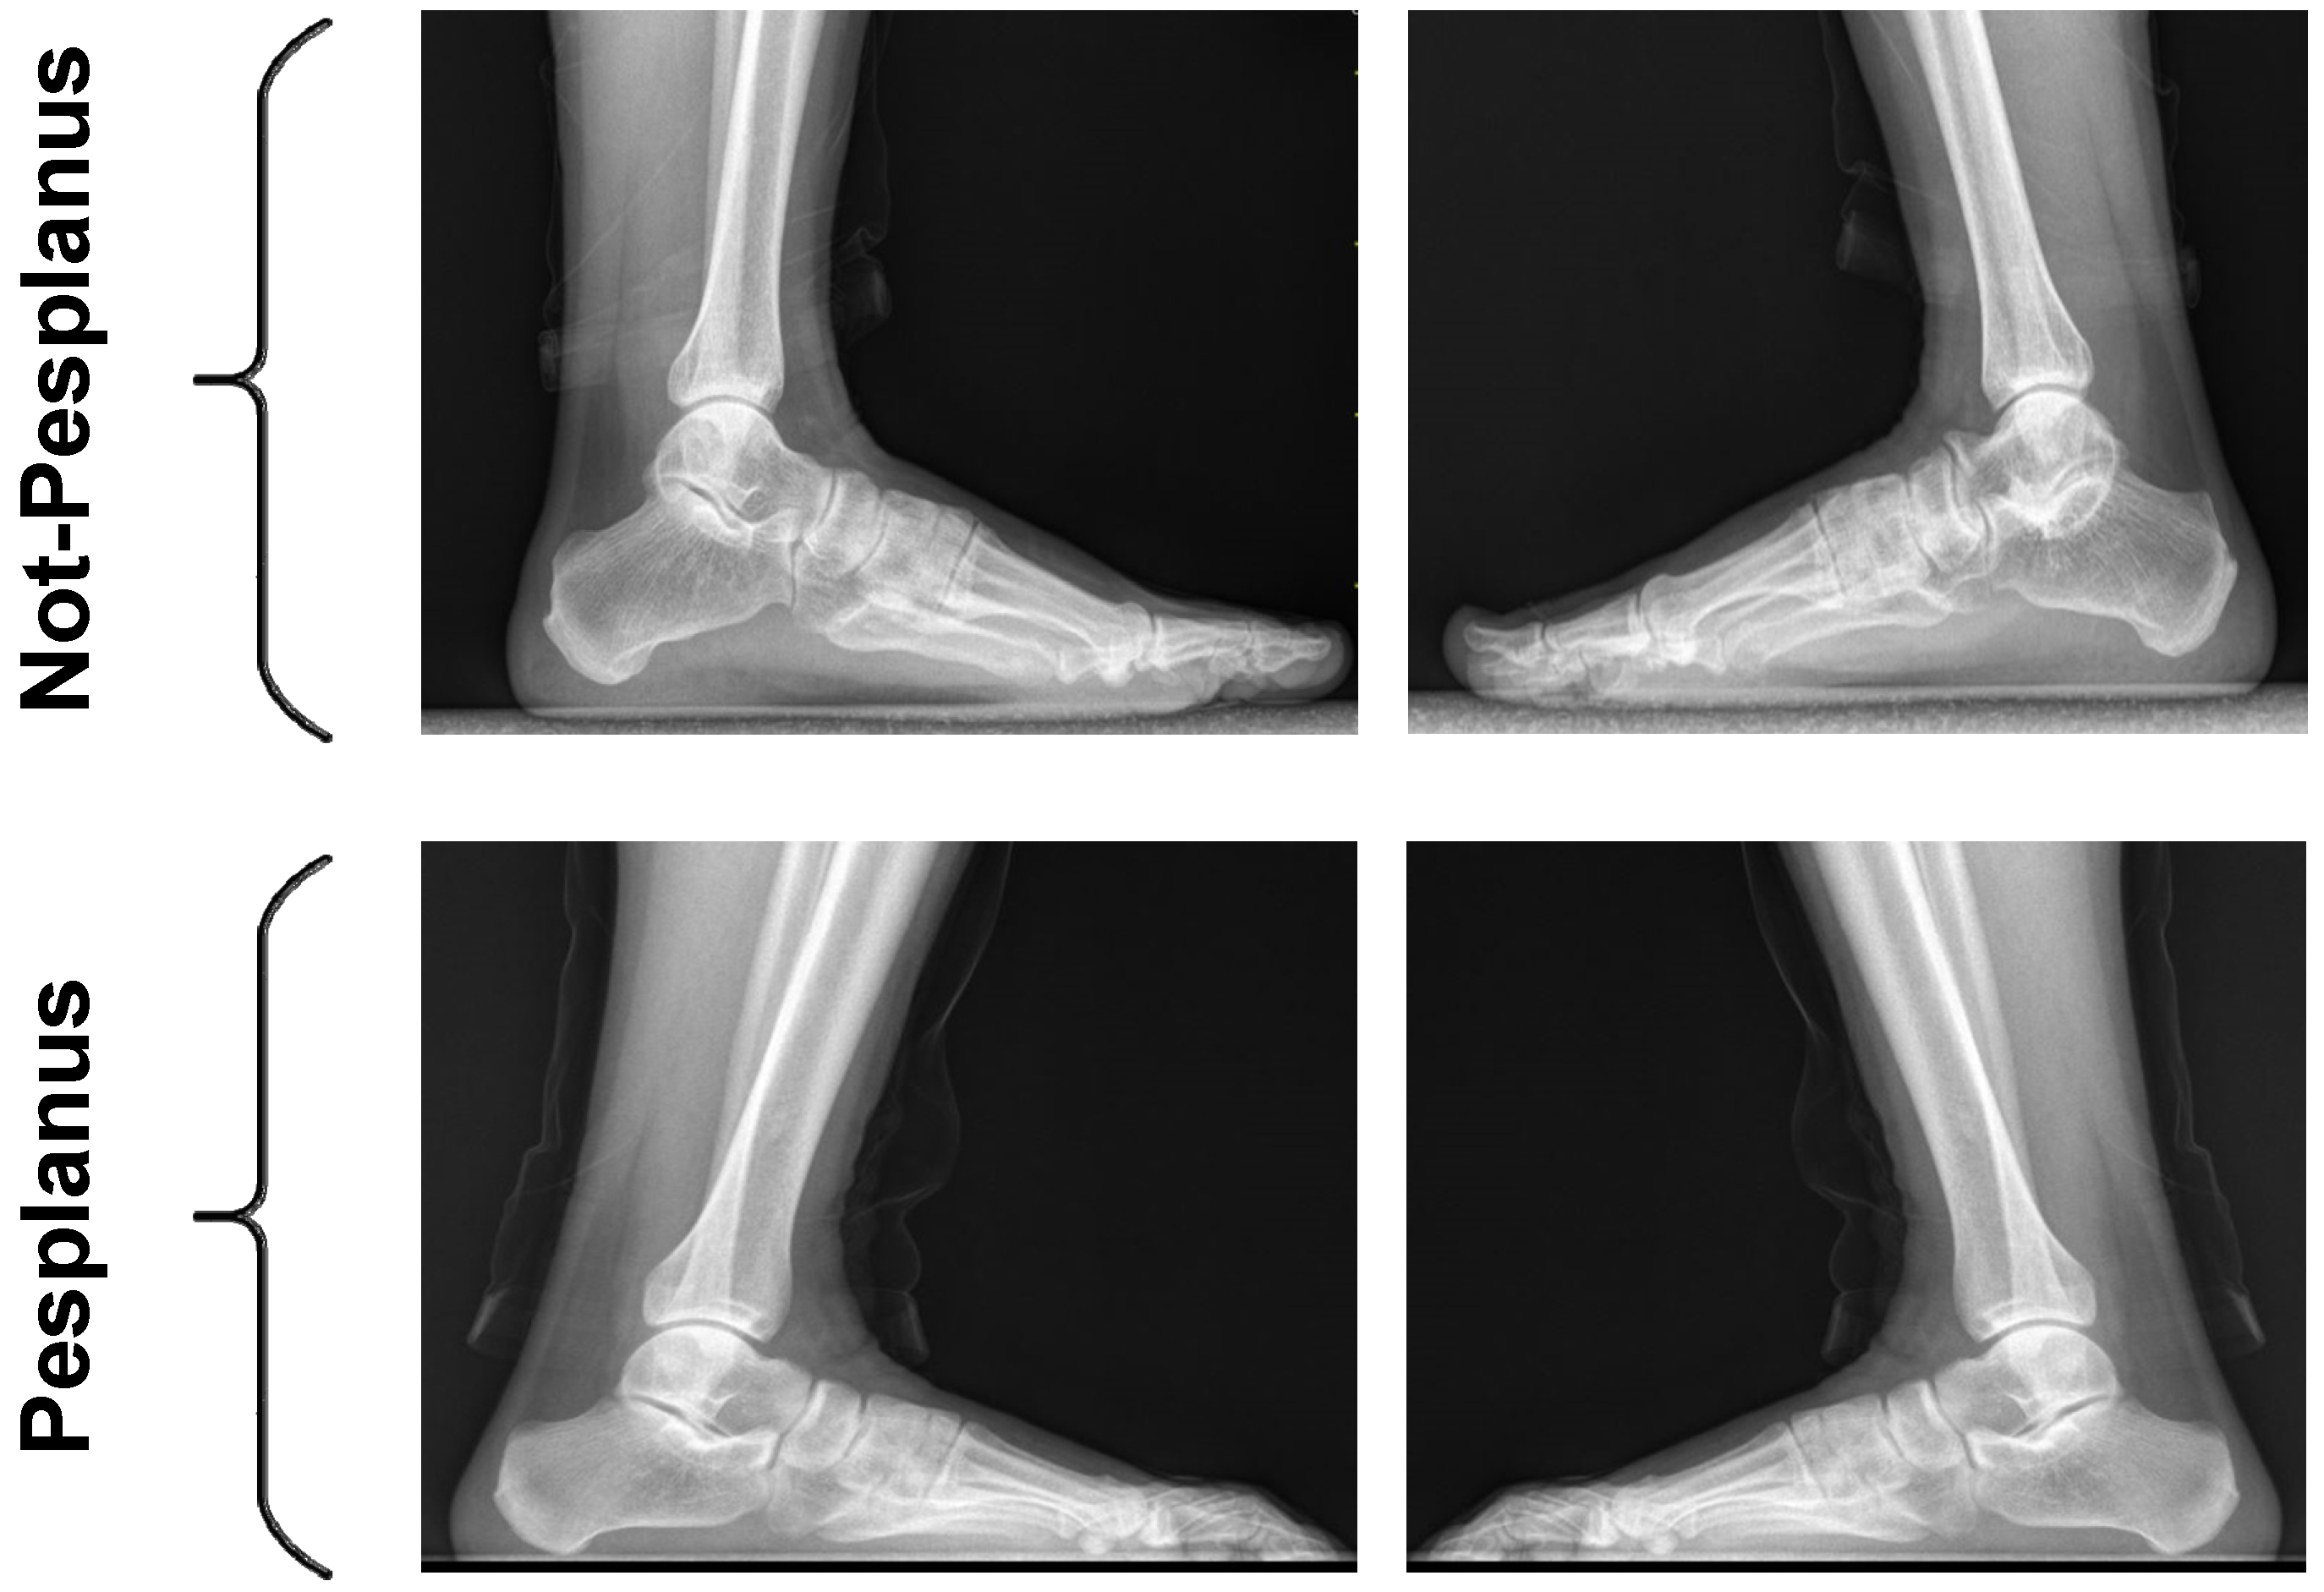

2.1. Used Pes Planus Image Dataset